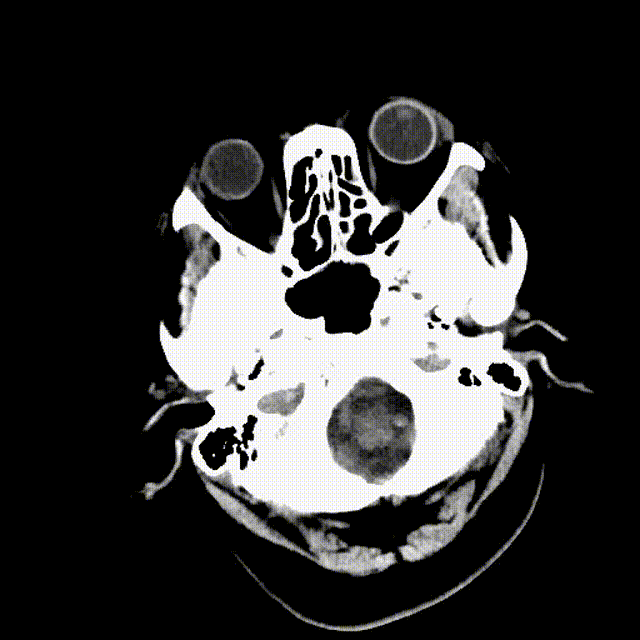

术前平扫CT/CTA

右侧颈内动脉闭塞

右侧颈总动脉造影见造影剂上行困难